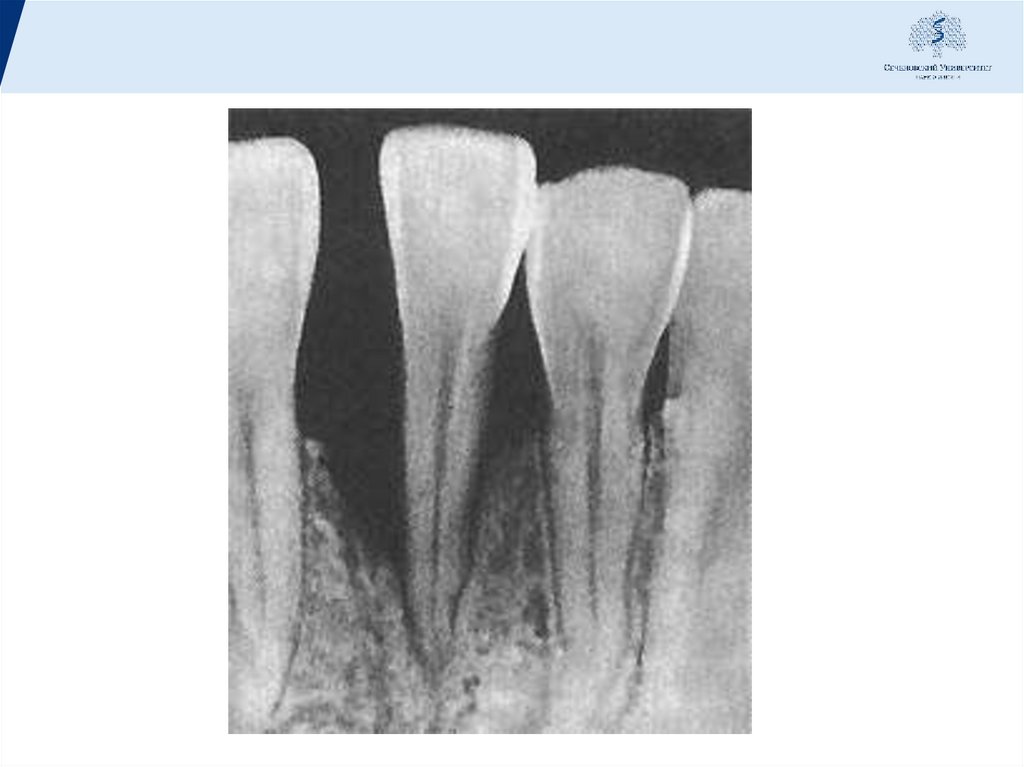

организма. на рентгенограмме определяются отсутствие

компактной пластинки на вершинах межзубных

перегородок, расширение периодонтальной щели в

пришеечной области, резкие очаги остеопороза и первые

признаки деструкции костной ткани.

Рентгенологическая картина характеризуется выраженным

остеопорозом и деструкцией кости, преобладает

вертикальный тип резорбции с образовантем костных

карманов. Параллельно развиваются изменения со стороны

В развившейся стадии пародонтита можно выделить I, II, III

степени заболевания. Критериями являются глубина

патологических карманов и степень резорбции костной ткани.

I степень: глубина карманов 3,5 мм и резорбция костной ткани

не более 1 /з длины корня зуба;

II степень: глубина карманов - до 5 мм, а резорбция костной

ткани до 1/2 длины корня;

III степень: глубина карманов более 5 мм, деструкция костной

ткани более чем на 1/2 длины корня зуба.